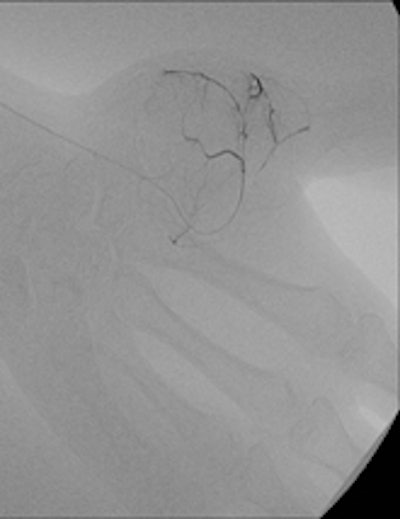

Bilbao's keen interest in interventional radiology began during the third year of his residency in 1982.

In the third year of my residency in 1982, I began to be attracted by the new way to perform interventions through percutaneous and endovascular approaches, and for a few months I went to the MD Anderson Center in Houston, Texas, U.S. There I took an important decision, which was that I would like to be completely involved in interventional radiology (IR), and with the great support of the CUN, this is what I have done for the rest of my professional life.